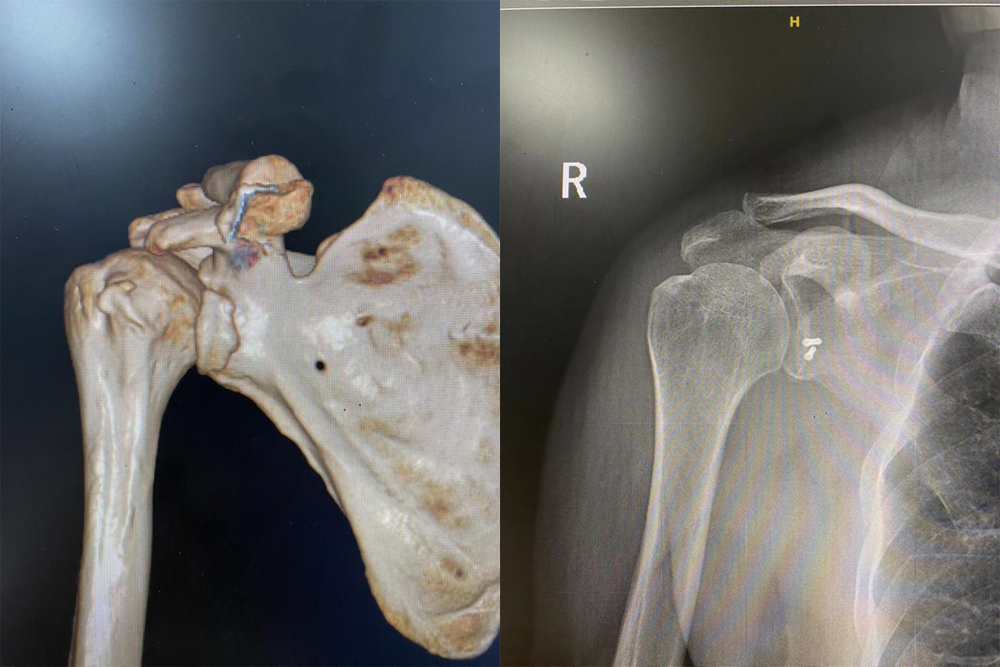

兰陵县人民医院关节外科成功实施一例肩胛盂骨折手术。患者因车祸入院,肩关节CT检查后发现肩胛盂前唇骨折。在查体过程中肩关节极度不稳,恐惧试验阳性,考虑关节盂不完整且关节囊撕裂,决定为其实施手术治疗。科室团队经过充分的术前讨论,快速制定手术方案,医护团队密切配合,完成小切口治疗肩胛盂骨折,手术经三角肌胸大肌间沟入路,保护肩胛下肌,通过两枚空心钉固定关节盂前唇骨块,并紧锁缝合关节囊。术中活动肩关节,稳定、无脱位,骨折重新获得了良好的复位及固定。术后指导患者功能康复,患者右上肢功能恢复良好。